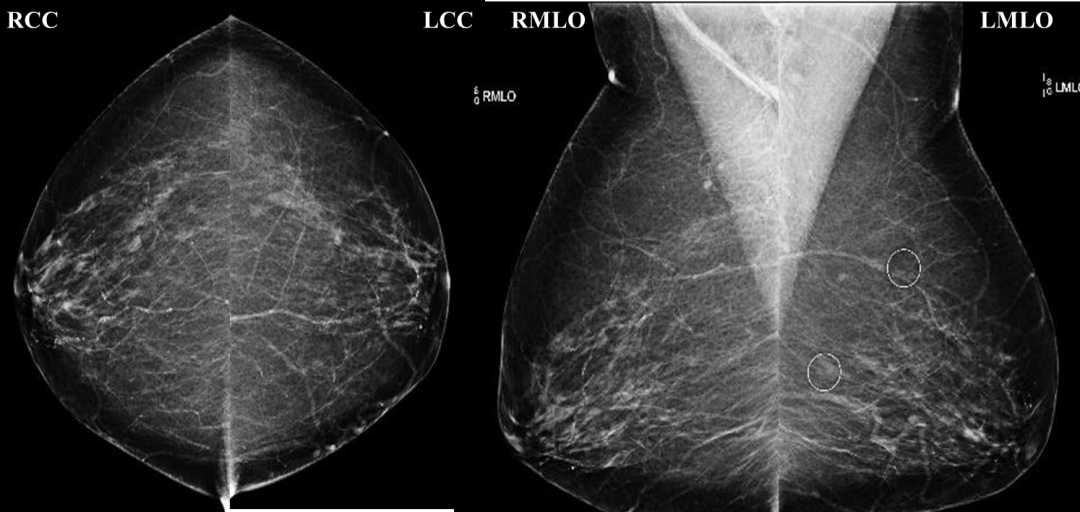

乳腺钼靶检查系统是一种低剂量乳腺X光拍摄乳房的技术,它能清晰显示乳腺各层组织,可以发现乳腺增生,各种良恶性肿廇以及乳腺组织结构紊乱,可观察到小于0.1毫米的微小钙化点及钙化簇,是早期发现、诊断乳腺癌的最有效和可靠的方式,尤其对于临床不可能及的,以微小钙化簇为唯一表现的早期乳腺癌具有特征性的诊断意义,对乳腺癌的诊断敏感性为82%~89%,特异性为87%~94%。乳腺钼靶检查系统具有成像清晰、检查操作方便快捷、辐射量小等特点,该仪器检查诊断可准确发现乳腺增生、病变、包块、钙化的形状、大小、密度、性质等。与超声、磁共振乳腺检查,相互补充,大大提高疾病诊出率,被誉为国际乳腺疾病检查的“金标准”。